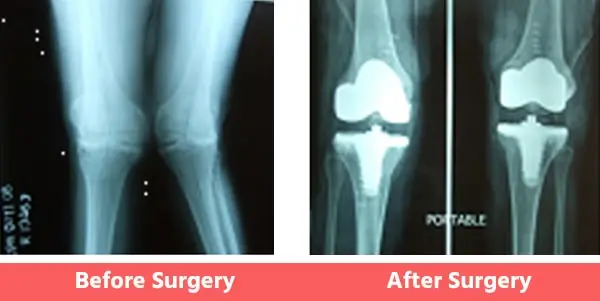

People may have certain deformities of the knee which include bow legs (varus), knock knees (valgus), or even wind-swept legs.

In such cases, the surgeon has to be well-experienced in handling such cases and should also have had considerable experience with revision joint replacement surgeries as well. See below Images.

2. Knock Knees (Valgus)

Some Common Deformities

You can see illustration and X-Ray images shown above already.